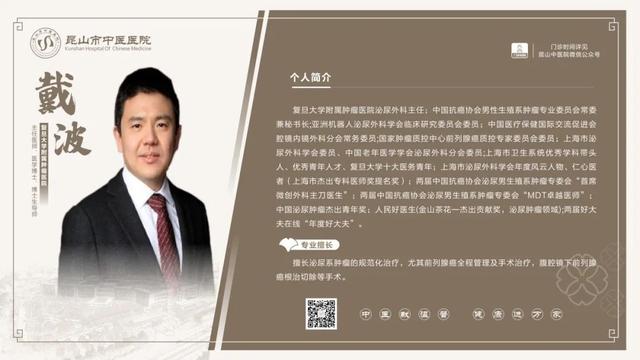

6��23��-6��29��������ר�ҳ���һ����

6��23��-6��29�������dz���ר�ҽ���